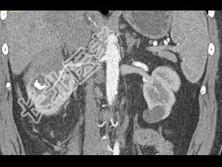

- 单项选择题根据所提供的图像,最可能的诊断是 ( )

A、胰腺脂肪瘤

B、正常胰腺

C、胰腺癌

D、胰腺转移癌

E、以上都不是